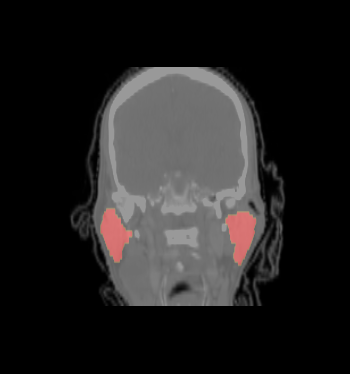

- We selected the ROI of every data excluding lung and chest. For each data there exist the segmentations of brain stem, left and right parotids. For example

- We constructed the average atlas of 20 datasets of ROI, and merged the segmentations into the average atlas. These segmentations are the probability maps of

brain stem, left and right parotids.